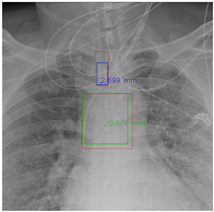

Figure 7 and Figure 8 demonstrate the effect of post-processing. The red bboxes and points in these figures are the GT ETT/bifurcation bboxes and the position of GT ETT tip/Carina, respectively. The green polygon is the GT mask of the ETT and the bifurcation. The blue bbox and point are the predicted ETT bbox and ETT tip, respectively. The yellow bbox and point are the predicted bifurcation and Carina, respectively. Specifically, without the post-process, the model might leave more than one predicted ETT tip/Carina, such as where the red arrow points in Figure 7a. However, with the post-process, the extra points would be removed as shown in Figure 7b. Besides, with the refinement process in the post-process, the feature point of ETT tip/Carina could be further refined as shown in Figure 8. Concretely, the object error of Carina was corrected from 8.469 mm to 1.319 mm.

Figure 8.

Refining the feature point of ETT tip/Cairna by the bbox of ETT/Bifurcation. (a) Without post-process. (b) With post-process.